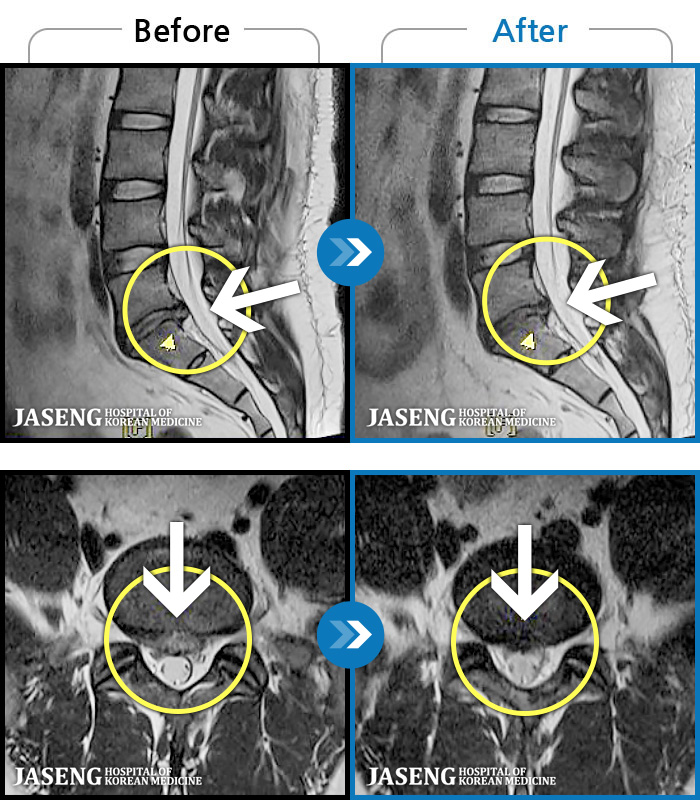

[] 03.04.01~09.11.01

ȯںп Ǹ ǿ ԿǾ, ο ġ ۿ Ƿ ġḦ Ͻñ ٶϴ.